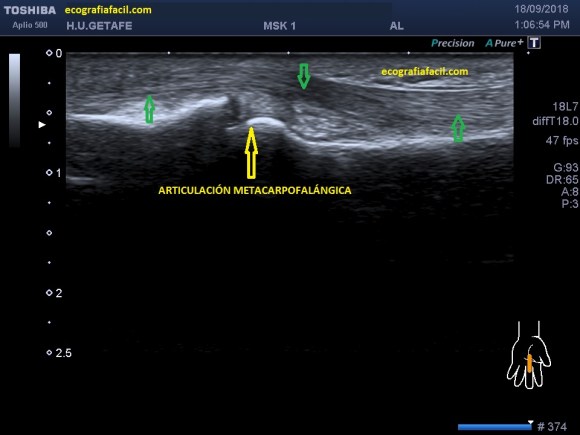

En el protocolo de exploración testicular te contaba cómo había que hacerlo y la semiología normal habitual.

Tenemos que tener claro que el testículo debe verse hiperecogénico y homogéneo y partiendo de esta premisa, realizar los cortes necesarios estudiando la anatomía testicular, incluyendo siempre, testes, epidídimo, cubierta y paquete vascular, es decir, dentro de la bolsa escrotal no nos dejamos nada sin ver.